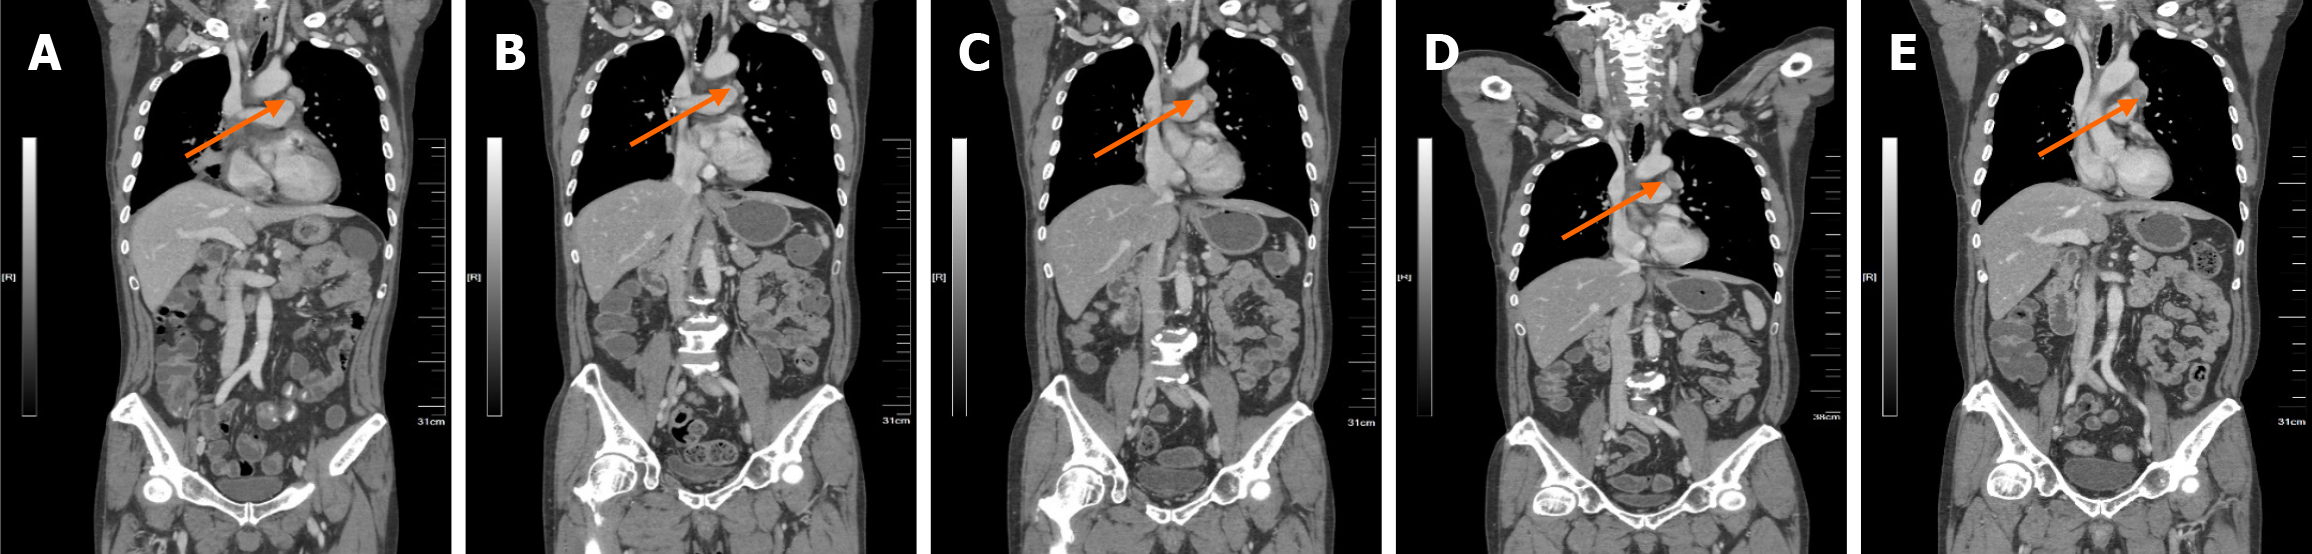

Figure 4 Enhanced computed tomography showed the follow-up of the left diaphragmatic angle lymph node.

A: On May 31, 2023; B: On May 7, 2024; C: On July 10, 2024; D: On September 11, 2024; E: On November 11, 2024. The orange arrows in the figures point to the metastatic left diaphragmatic angle lymph node.